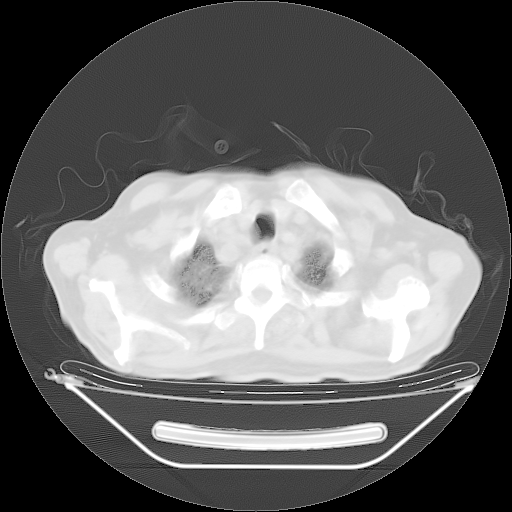

今天复查肺部CT,发现双肺广泛磨玻璃样改变。所以我把3月19日和5月9日相隔50天的肺部CT上传。请大家会诊。

2009年3月19日肺部CT片。

2009年3月19日肺部CT